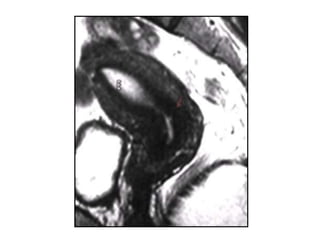

Útero arcuato

 Indentación suave del miometrio en la cavidad

endometrial a nivel de fundus.

 El contorno externo es normal (convexo).

 Algunos autores consideran que más que una

malformación podría tratarse de una variante

de la normalidad.